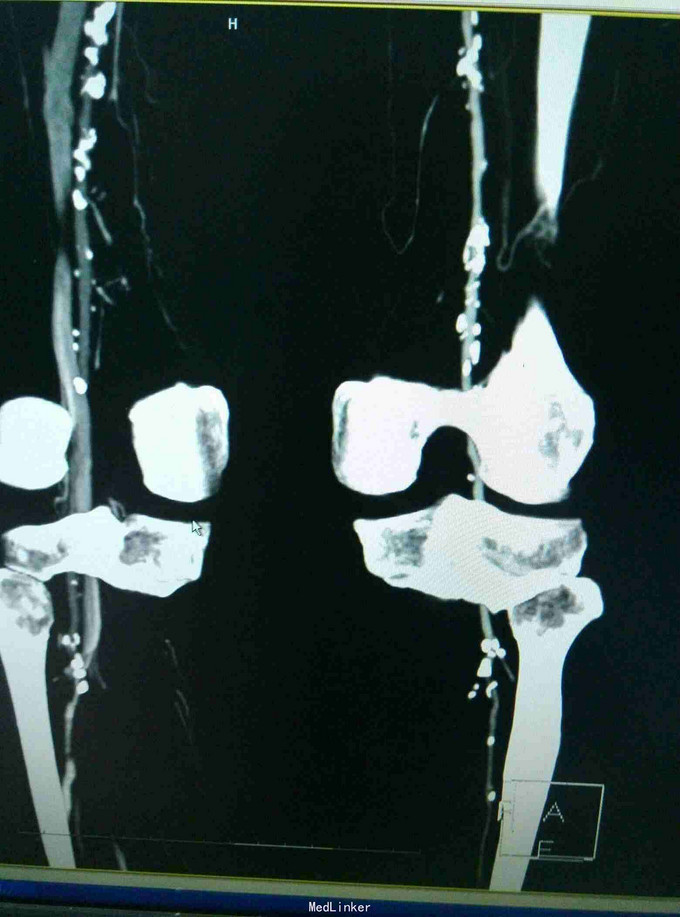

左下肢皮温降低,左足背可见紫红色淤斑,左股动脉扪及微弱波动。下肢血管成像提示:双下肢动脉节段性不同程度狭窄、闭塞。

双下肢动脉硬化闭塞症 手术:左侧髂动脉探查术,术中探查股动脉,导丝导管尝试通过闭塞段髂动脉,但反复尝试无法继续。右侧也无法通过。家属放弃。